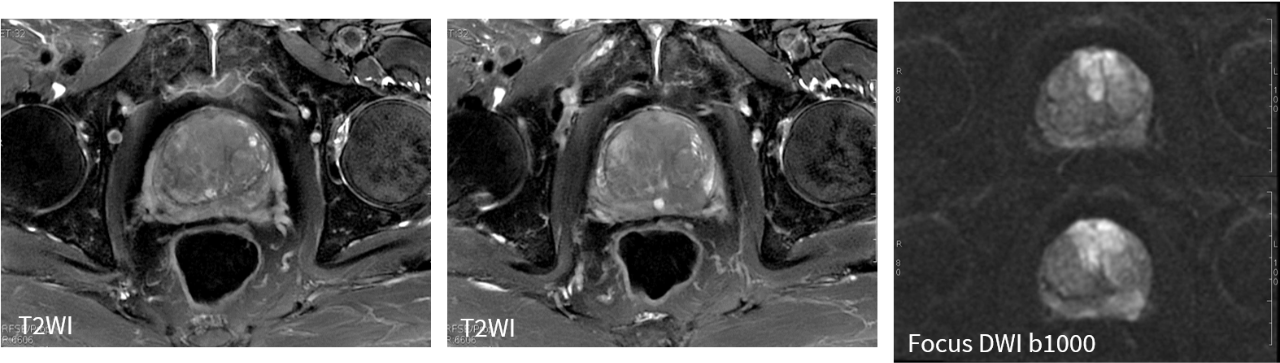

★图像质量高清!实现精准临床科研成像,高清的图像质量,可实现微小病灶的精细显示与分析,让病灶无处遁形,尤其在肿瘤和损伤的诊断方面独具优势。

★应用范围更广!能够完成包括神经系统、胸部、腹部、盆腔、心血管、骨骼关节、软组织、乳腺等全身各部位磁共振检查。